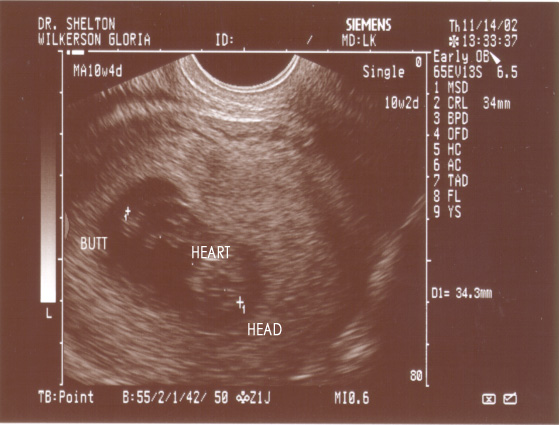

PICTURE 2:

The second picture, just a couple of

minutes later here shows our baby, and

it's swung itself around 180 degrees!